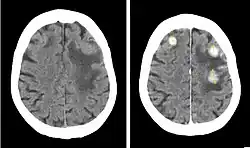

Iobitridol (trade name Xenetix) is a pharmaceutical drug used as an iodine-based radiocontrast agent in X-ray imaging.[1] It is injected into blood vessels, joints, or body cavities such as the uterus, and filtered out by the kidneys.[2] Its most common adverse effect is nausea. Severe allergic reactions are rare.[1][2]

Iobitridol is used for intravenous urography (imaging of the urinary system via a vein), angiography (imaging of blood vessels), angiocardiography (heart and coronary arteries), arthrography (joints), hysterosalpingography (uterus and fallopian tubes), and imaging of the cranium and the whole body.[2] It is approved for use in adults and children.[5]

Iobitridol is an iodine-containing radiocontrast agent.[2][5] The iodine atoms readily absorb X-rays, resulting in better contrast in radiography images.[9] The quality of images made with this drug is equally good as with other low– or medium–osmolarity iodinated contrast agents such as iopamidol or iohexol.[5]